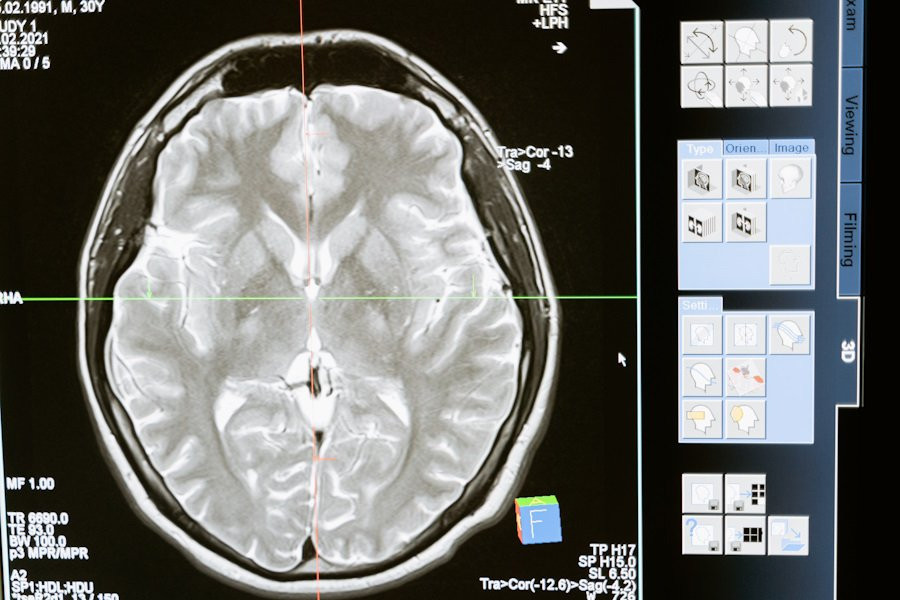

Фото из открытых источников

Воспользовавшись функциональной МРТ (фМРТ), специалисты определили конкретную область мозга, отвечающую за руминацию, — это дорсально-медиальная префронтальная кора (ДМПК).

Исследование показало, что ДМПК взаимодействует с другими частями мозга, особенно с левой нижней лобной извилиной и правым височно-теменным соединением. Данная связь играют немаловажную роль в понимании процесса руминации, поскольку эти области мозга связаны с речью и оценкой социальных ситуаций.

Учёные отмечают, что руминация представляет собой одну из наиболее важных моделей мышления, и их исследование показывает, что склонность к ней может быть связана с определенными связями в мозгу, которые можно измерить с помощью фМРТ. Они планируют использовать нейровизуализацю для отслеживания и управления психическим здоровьем.